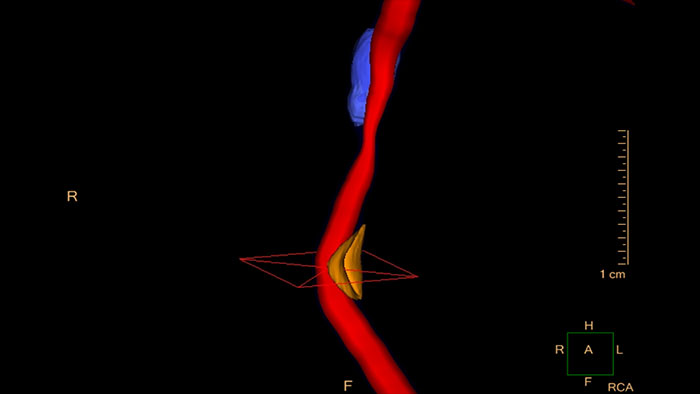

Evaluate coronaries plaque

Assess plaque sites using CT Cardiac Plaque Assessment. This application supports quantification and analysis of coronary plaque.